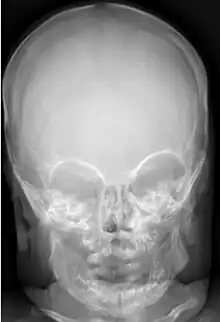

Macrocephaly (right) vs. normocephaly (left)

Many people with abnormally large heads or large skulls are healthy, but macrocephaly may be pathological. Pathologic macrocephaly may be due to megalencephaly (enlarged brain), hydrocephalus (abnormally increased cerebrospinal fluid), cranial hyperostosis (bone overgrowth), and other conditions. Pathologic macrocephaly is called "syndromic", when it is associated with any other noteworthy condition, and "nonsyndromic" otherwise. Pathologic macrocephaly may be caused by congenital anatomic abnormalities, genetic conditions, or by environmental events.[3]